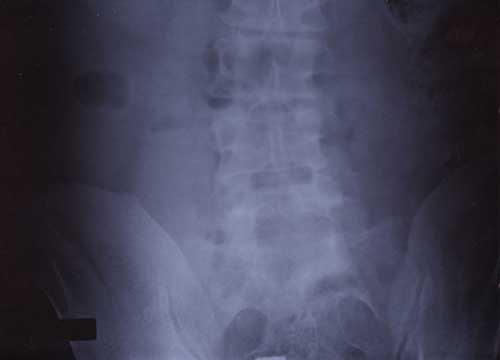

X Rays

Pancreatitis Information